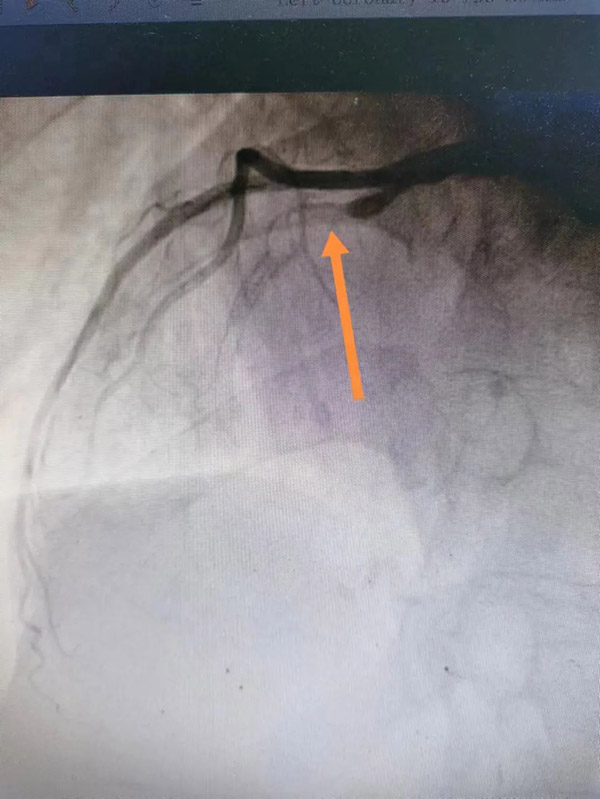

术前 术后

15时34分,患者被推入导管室,虽然已经做了术前评估和心理准备,但一到实操,大家还是如履薄冰。在佟主任带领下,团队充分发挥协作精神,改变惯有思维,谨慎操作。冠脉造影示:主要血管LAD开口90%狭窄,狭窄后100%闭塞,佟主任经慎重考量,经冠脉内溶栓及血栓抽吸,最后在LAD中远端置入支架一枚,血管顺利开通,TIMI血流3级,患者转危为安,大家如释重负。 术后患者被转入CCU病房,李海宁主任带领重症医学团队给予密切观察及术后精准治疗,使患者平稳度过危险期!3天后,患者安返普通病房,“太感谢你们了,是你们把我妈从鬼门关拉回来了啊”,每当管床医生李宏泽、护士长杨天舒查房时,李阿姨的孩子就兴奋对医生护士表示感谢。